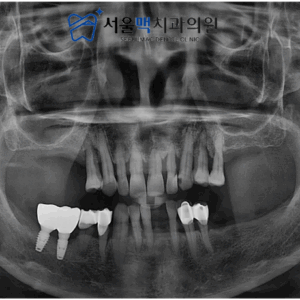

12. 가양역임플란트 상악동 거상술과 뼈 이식으로 단단한 임플란트를!

가양역임플란트 상악동 거상술과 뼈 이식으로 단단한 임플란트를!   안녕하세요. 서울맥치과 입니다:) ​ 최근에는 임플란트를 식립하는 것에 대한 부담과 걱정이 줄어들고, 자연치아와 비슷한 저작능력과 심미적인 면, 구강관리하는데 편리한 점 등의 장점으로 임플란트 수술사례가 많이 늘어났습니다.   이러한 임플란트의 좋은 인식과 덴탈 지식에 대한 수준이 높아진 것에 대해 기쁜 마음과 함께 환자분들께서 더보기…